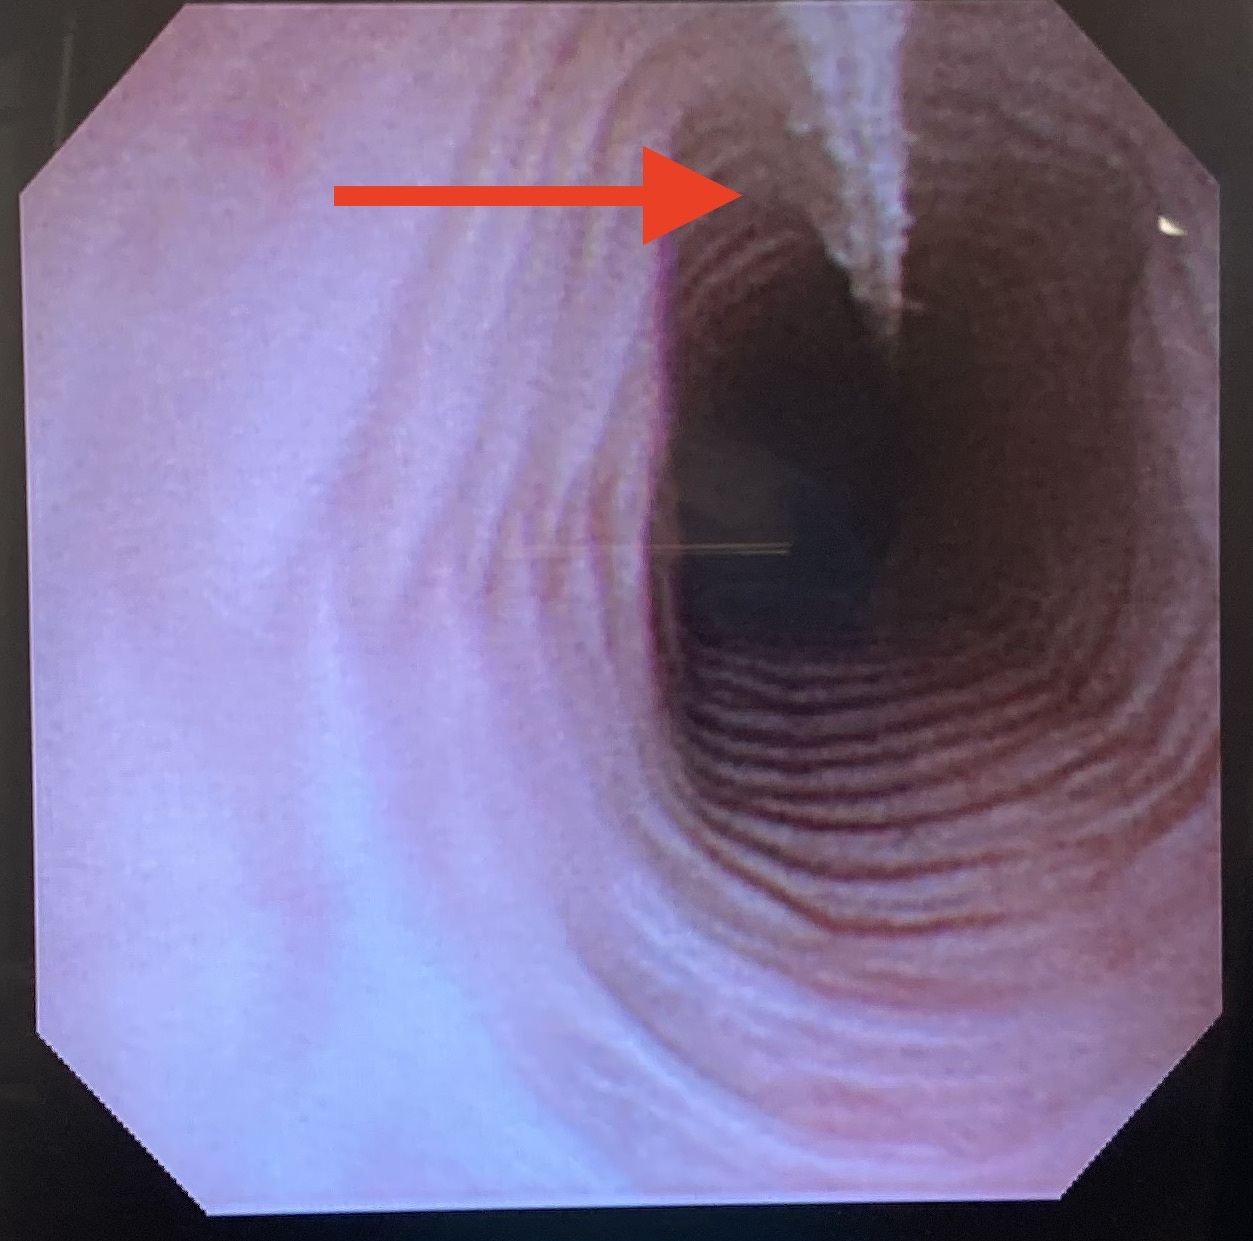

内視鏡で確認すると、食道内から(上の写真の赤矢印)胃の出口の幽門まで(下の写真の赤矢印)白い糸が入り込んでいて、引っ張っても抜けません。このようになると、無理に引っ張ると胃腸を切り裂いてしまうため、手術によってひも状異物を摘出する必要があります。